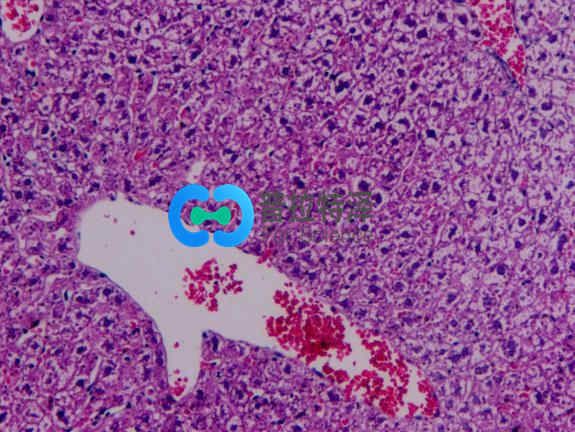

非酒精性脂肪性肝?。?/span>NAFLD)是一種無酒精濫用的肝病綜合征,包括單純性脂肪肝、脂肪性肝炎、脂肪性肝纖維化和肝硬變??蓮膯渭冃灾靖谓?jīng)非酒精性脂肪性肝炎(NASH)發(fā)展為肝纖維化,甚至導(dǎo)致肝硬化、肝細(xì)胞癌(HCC)或肝功能衰竭等終末期肝病。

小劑量鏈脲佐菌素結(jié)合高脂飲食,已被用于制備小鼠的NAFLD,可導(dǎo)致脂肪變性,炎癥,纖維化甚至肝細(xì)胞癌。四氯化碳(CCl4)可造成肝損傷,可單獨(dú)施用或配合高脂飲食來誘發(fā)脂肪肝或肝纖維化。其機(jī)制主要是CCl4誘導(dǎo)肝臟發(fā)生氧化應(yīng)激反應(yīng),導(dǎo)致有害的脂質(zhì)和蛋白質(zhì)過氧化產(chǎn)物不斷產(chǎn)生和積累,并發(fā)生嚴(yán)重的壞死反應(yīng),從而導(dǎo)致肝細(xì)胞結(jié)構(gòu)和功能破壞。這種方法造模時(shí)間較短,但是發(fā)病機(jī)制、病程變化及組織學(xué)形態(tài)與人類脂肪肝存在較大差異,并且藥物毒性強(qiáng),易致動物死亡。